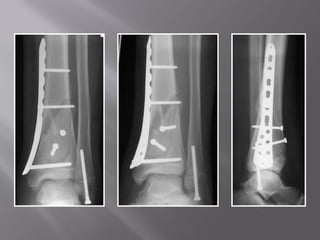

2 year follow up

 Never plated

 Treat with

fixator

 Bone graft less